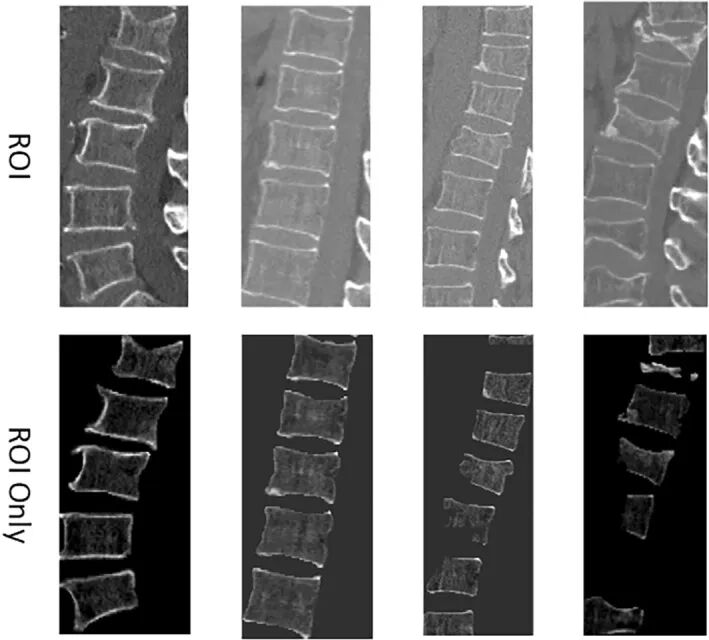

回顾性收集了2015年1月至2022年10月在3个医学中心383例患者(训练集=240例骨质疏松性椎体压缩性骨折(OVCF),验证集=63,测试集=80)的CT图像和临床信息。采用U-net模型对感兴趣区域进行自动分割。对所有脊柱区域进行三维剪切,获得最终的ROI区域,包括3D_Full和3D_RoiOnly。利用Densenet 121-3D模型对裁剪区域进行建模,同时建立T-NIPT预测模型。通过构建ROC曲线来评估深度学习模型的诊断性。我们生成校准曲线,以评估校准性能。此外,决策曲线分析(DCA)被用来评估预测模型的临床效用。

分割结果可视化

本文提出的后处理方法有效识别并剔除了因体素分类离散性产生的异常分割区域,从而提升了模型的整体分割精度。